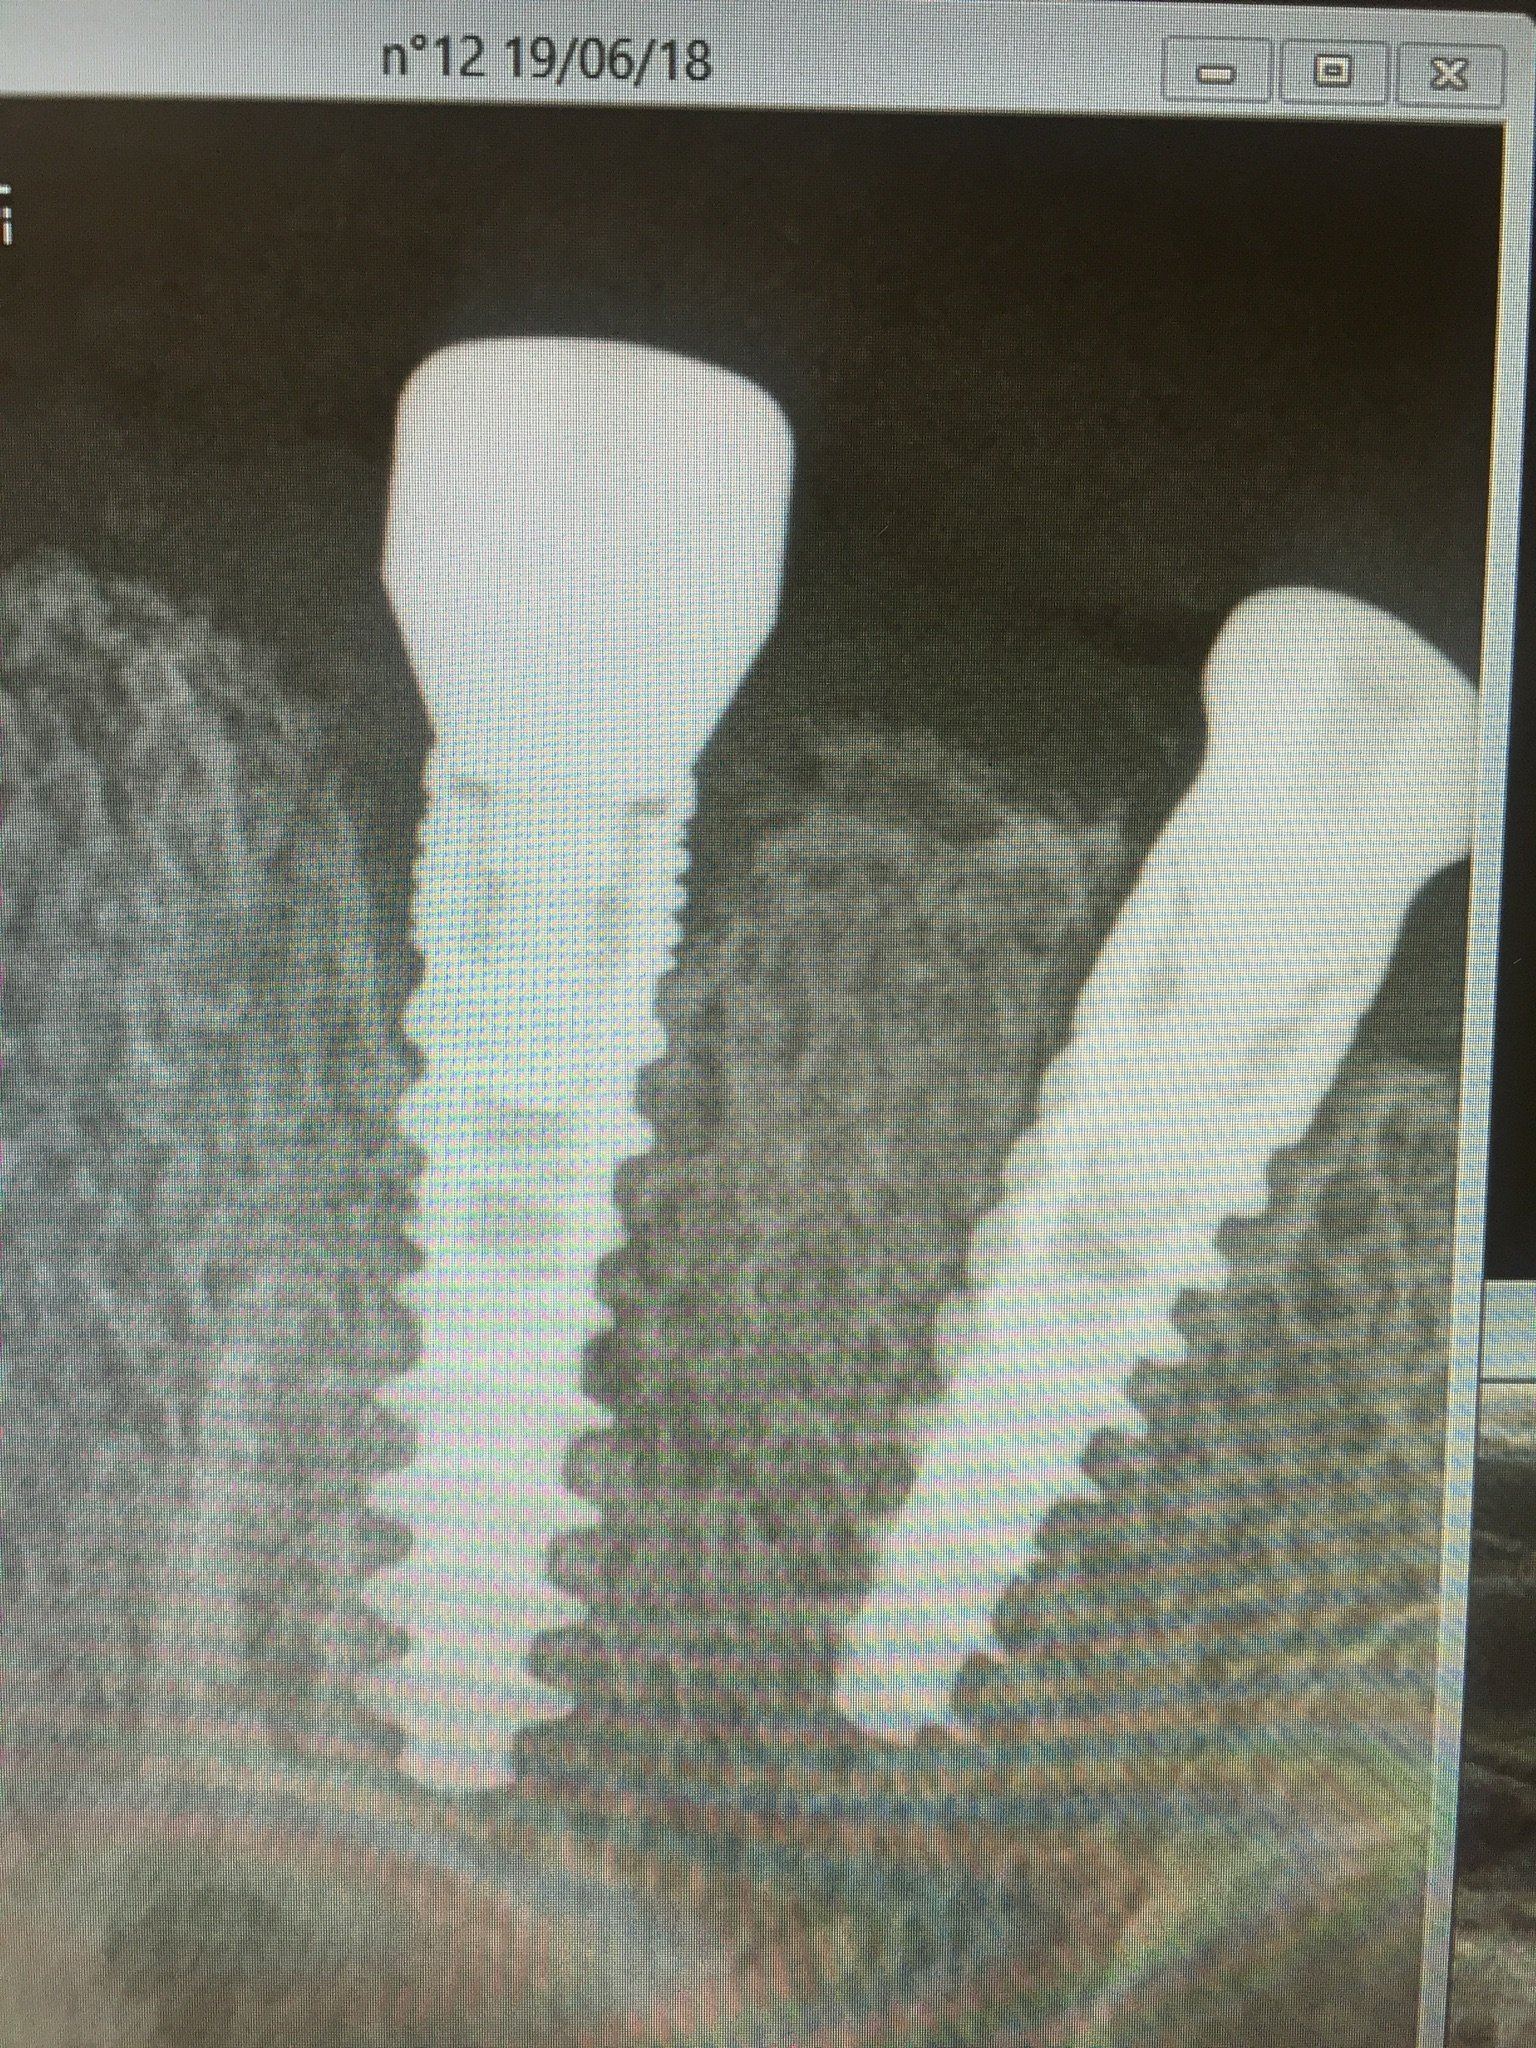

Por favor a ver si alguno sabéis cual es el implante del 12. El paciente se lo colocó en otra clínica y han desaparecido. Conexión interna pero cuadrada (os mando [...]